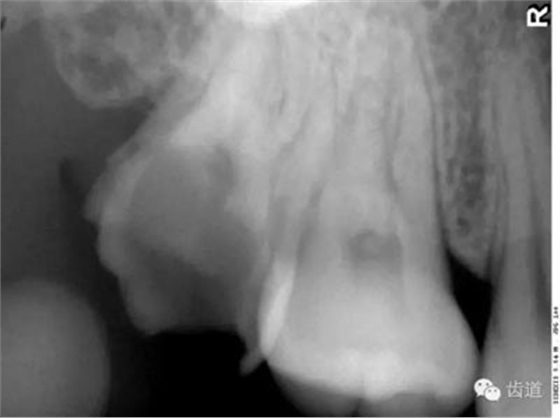

在投照上頜磨牙根尖片時(shí),經(jīng)??梢钥吹窖栏戏接幸幻芏鹊偷挠跋?,為上頜竇的一部分,邊緣環(huán)繞以密度高的線狀影像,為上頜竇壁致密骨層。有時(shí)可見上頜竇的分隔。